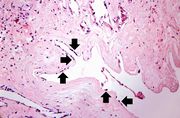

| 16:36, 19 August 2013 | IPLab4Thrombosis3.jpg (file) | 81 KB | Seung Park | This is a higher-power photomicrograph of the ruptured fibrous cap (arrows) with hemorrhage (1) into the atherosclerotic plaque. | 1 | |